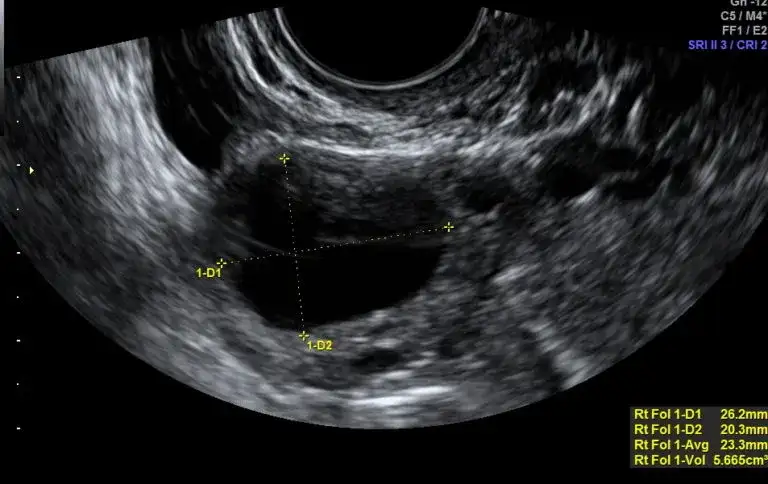

USG po owulacji co widać: kluczowe zmiany w jajnikach i macicy

Zobacz, co można zaobserwować na USG po owulacji. Dowiedz się o kluczowych zmianach w jajnikach i macicy, które wpływają na płodność.